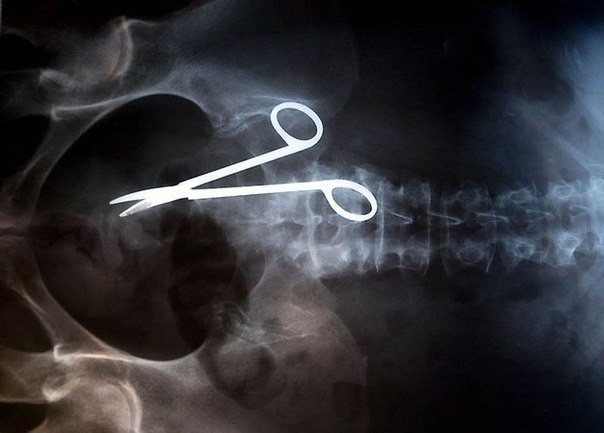

Самые причудливые рентгеновские снимки в истории медицины. Некоторые из них жуткие и пугающие, возможно часть из них вызовет у вас шок. Трудно поверить в то, что это правда, однако снимки говорят сами за себя.. 1) Череп китайского мужчины, который был уби8 写真